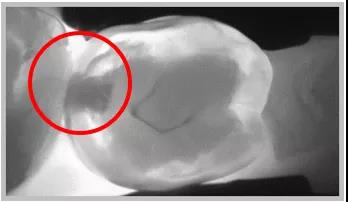

龋齿探测

龋齿探测仪检查:在龋齿探测仪的咬合面的图像上显示,近中合面存在低密度的阴影区。判断有邻面龋。